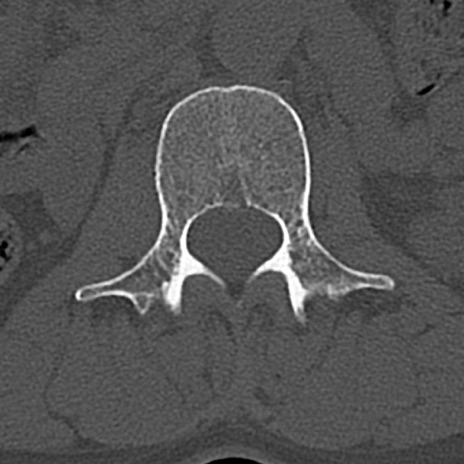

腰椎CT

横断像と矢状断像